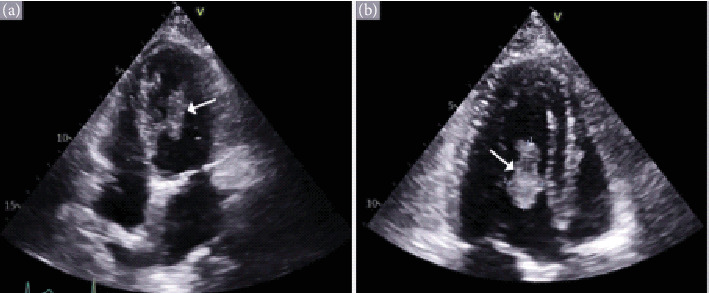

Background: Cardiac metastases, though more common than primary cardiac tumors, remain under-recognized due to their often subtle clinical presentation. These tumors can lead to life-threatening complications, and their diagnosis is typically delayed. Objective: This paper is aimed at reviewing two distinct cases of metastatic cardiac tumors, shedding light on diagnostic challenges, clinical presentations, and management approaches. Methods: We present two cases of patients with metastatic melanoma and undifferentiated malignant spindle cell neoplasm, respectively. Diagnostic imaging, including echocardiography and PET scans, was used to identify the cardiac masses, and biopsy results provided histopathological confirmation. Treatment plans involved systemic immunotherapy, chemotherapy, and surgical resection. Results: In both cases, cardiac metastases were detected through advanced imaging, despite the patients presenting with nonspecific symptoms like abdominal pain and shortness of breath. The metastatic tumor in one patient responded to immunotherapy before surgical excision, while the other patient, in advanced stages, opted for supportive care. Conclusion: Cardiac metastasis should be considered in cancer patients who present with unexplained cardiac symptoms. A multidisciplinary approach, including imaging and biopsy, is crucial for accurate diagnosis. Despite aggressive treatment, the prognosis remains poor, emphasizing the need for early detection and better therapeutic strategies.

Abstract Image